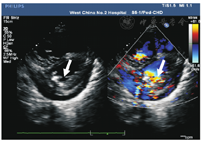

本组28例IE患儿中,3例出现瓣膜穿孔(图2),包括2例为二尖瓣前叶穿孔,1例为三尖瓣前叶穿孔;1例为二尖瓣后叶腱索断裂;6例为二尖瓣大量反流、3例为三尖瓣大量反流、1例为主动脉瓣大量反流;1例为心包积液。其余13例患儿心脏瓣膜检查未见异常。